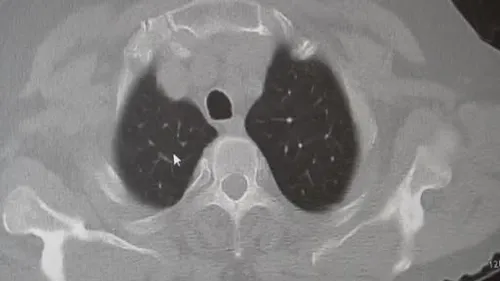

KOAH ve zatürre uyarısı: Prof. Dr. Sait Karakurt'ın değerlendirmesi Prof. Dr. Sait Karakurt (Marmara Üniversitesi Pendik Eğitim ve Araştırma Hastanesi Göğüs Hastalıkları Kliniği) KOAH ve zatürre konusunda toplum için önem taşıyan uyarılarda bulundu. Karakurt, vakaların yaklaşık yüzde 85’inin sigara kullanımına…